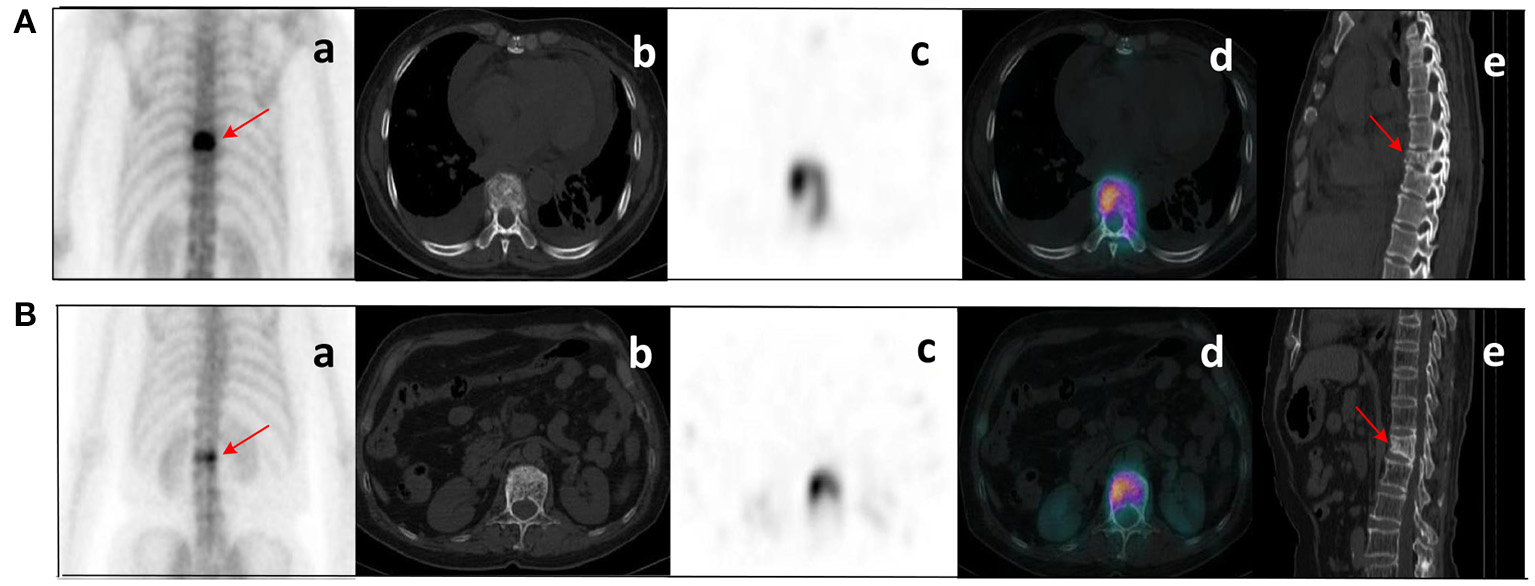

Figure 6

Clinical cases SPECT/CT images of bone metastases (A) and benign bone lesions (B). The images shown are WBS image, axial CT, SPECT, fusion image, and sagittal CT (a–e, respectively). (A) bone metastases: a 53-year-old female with an adenocarcinoma of the left lung. Wedge-like changes of the T8 vertebral body with an abnormal concentration of radioactive tracer (arrows). (B) benign bone lesions: a 68-year-old female with breast cancer. Wedge-like changes of the L1 vertebral body with higher bone density and increased radioactive tracer distribution (arrows). It was difficult to determine whether lesions were metastasis with conventional images only. Lesion (A) was confirmed as pathological fracture due to bone metastases by pathological examination and showed systemic bone metastases at subsequent imaging follow-up. Lesion (B) was confirmed to be a benign compression fracture by imaging follow-up and clinical information.